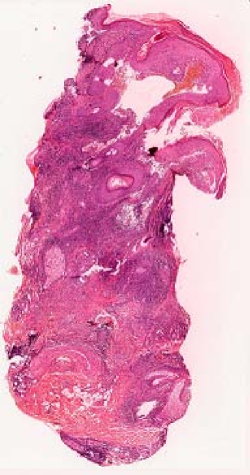

We demonstrate our WSI creation workflow on Leishmaniasis cases, as shown in Figures 1 and 4. An expert pathologist reviewed the cases and annotated granulomas as well as LD bodies on the stitched images and our generated images in Figure 4. To show generalizability of our approach, we also show results on core biopsies of breast, duodenum, stomach, liver, and lymph nodes (Figure 5).

Limitations. Our current model results in significant artifacts at the boundary of the tissue. We will address these and the square artifacts at the borders more rigorously using bi-direction feature fusion GANs [13]. In this work, we used just one microscope which was the cheapest-yet-clinical grade microscope available on market (in developing regions). In the future, we will compare our stitching results on microscopes from different vendors with different resolution cameras. We will also explore using smartphone cameras to acquire videos rather than microscope cameras. We currently require pathologists to pause between frames (ideally with > 50% overlap) to get the best-quality results. In the future, we will explore ways to handle stitching even from faster videos with minimal overlaps. We will also extend our stitching platform to immunohistochemistry-stained images where manual cell counting is tedious and more advanced deep learning approaches can play a critical role in more accurate, objective, reproducible, and faster protein expression quantification. Finally, we will develop deep learning algorithms for detecting granulomas and LD bodies specific to Leishmaniasis.